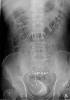

b) Urografia

Badanie urograficzne polega na podaniu specjalnego płynu nazywanego kontrastem dożylnie, który następnie wydalany jest przez nerki z moczem. Seria zdjęć

rentgenowskich (RTG) dzięki podanemu kontrastowi pozwala na uwidocznienie układu moczowego (układy

kielichowo-miedniczkowe nerek, moczowody i pęcherz moczowy). W większości przypadków guza pęcherza moczowego widoczny on jest jako ubytek wypełnienia.